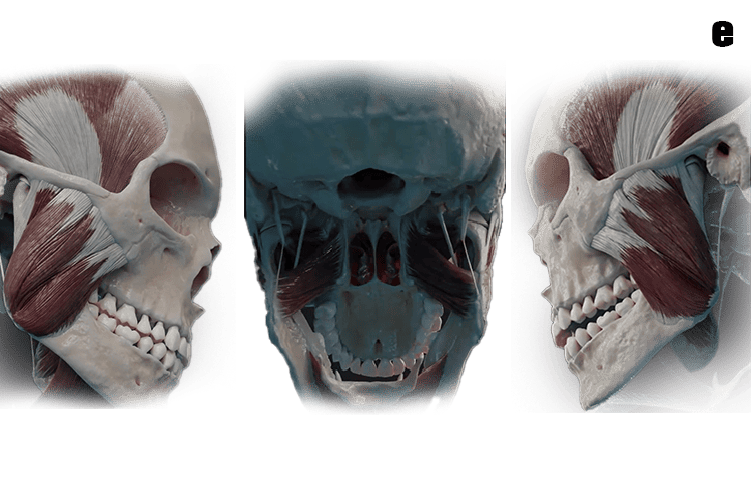

a. The TMJ is a sliding "ball and socket"  Joint located in front of each ear , where the upper & lower jaws meet. Its the joint that works when the mouth is opened and closed together.

b. The ball-shaped condyle on the lower jaw glides along the socket in the skull base when you open your mouth, and slides back when you close your mouth.

c. Inside the TM joint is a disc that provides a cushion between the upper and lower jaw when it is opened and closed.

d. Connective tissue (Retrodiscal tissue) containing blood vessels and nerves attach the disc to the joint.

e. Muscles attached to the jawbone control movement and position. and work together to open and close the mouth.

f. Ligaments hold and stabilize the joint.